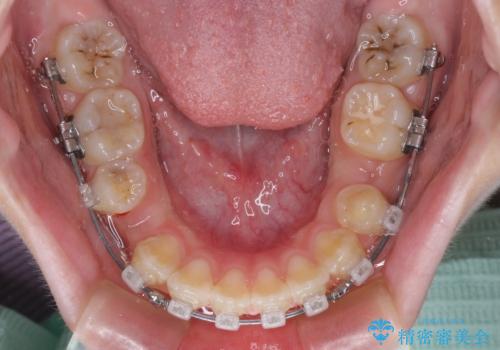

- クリアブラケット

- 1年4ヶ月

- 10-30回

当初は舌のトレーニングがうまくできていなかったのですが、途中から奏効し、非常に短い期間で治療を終えることができました。